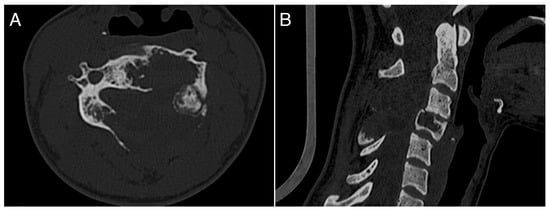

A 26-year-old female with a massively lytic lesion in C4 showed consistent ossification after seven months of treatment (Figure 2 and Figure 3). She chose to discontinue denosumab after 20 administrations due to being asymptomatic and being at her fertile age. However, ten months after stopping the medication, she experienced severe neck and upper left pain, leading her to seek urgent medical attention at the emergency department of our clinic. CT and MRI showed a local recurrence of the ABC in C4 (Figure 4 and Figure 5). She then received a “re-challenge” treatment with denosumab according to the above-mentioned protocol, and the treatment is still ongoing. At the last follow-up, 20 months after being on denosumab with a monthly schedule, the patient was asymptomatic, and the last CT showed good ossification of C4 (43 months follow-up from the first treatment).

Figure 2. A 26-years-old woman presented with neck pain and no neurological problems. MRI pattern was pathognomonic for ABC. (A): axial view; (B): sagittal view.